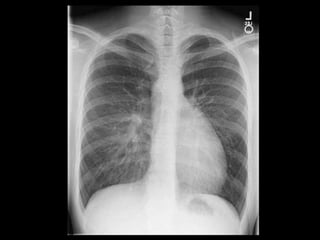

Chest X-ray

What could be the diagnosis

Lab Studies:

• CXR: prominent RV

• ECG: RVH, right axis deviation